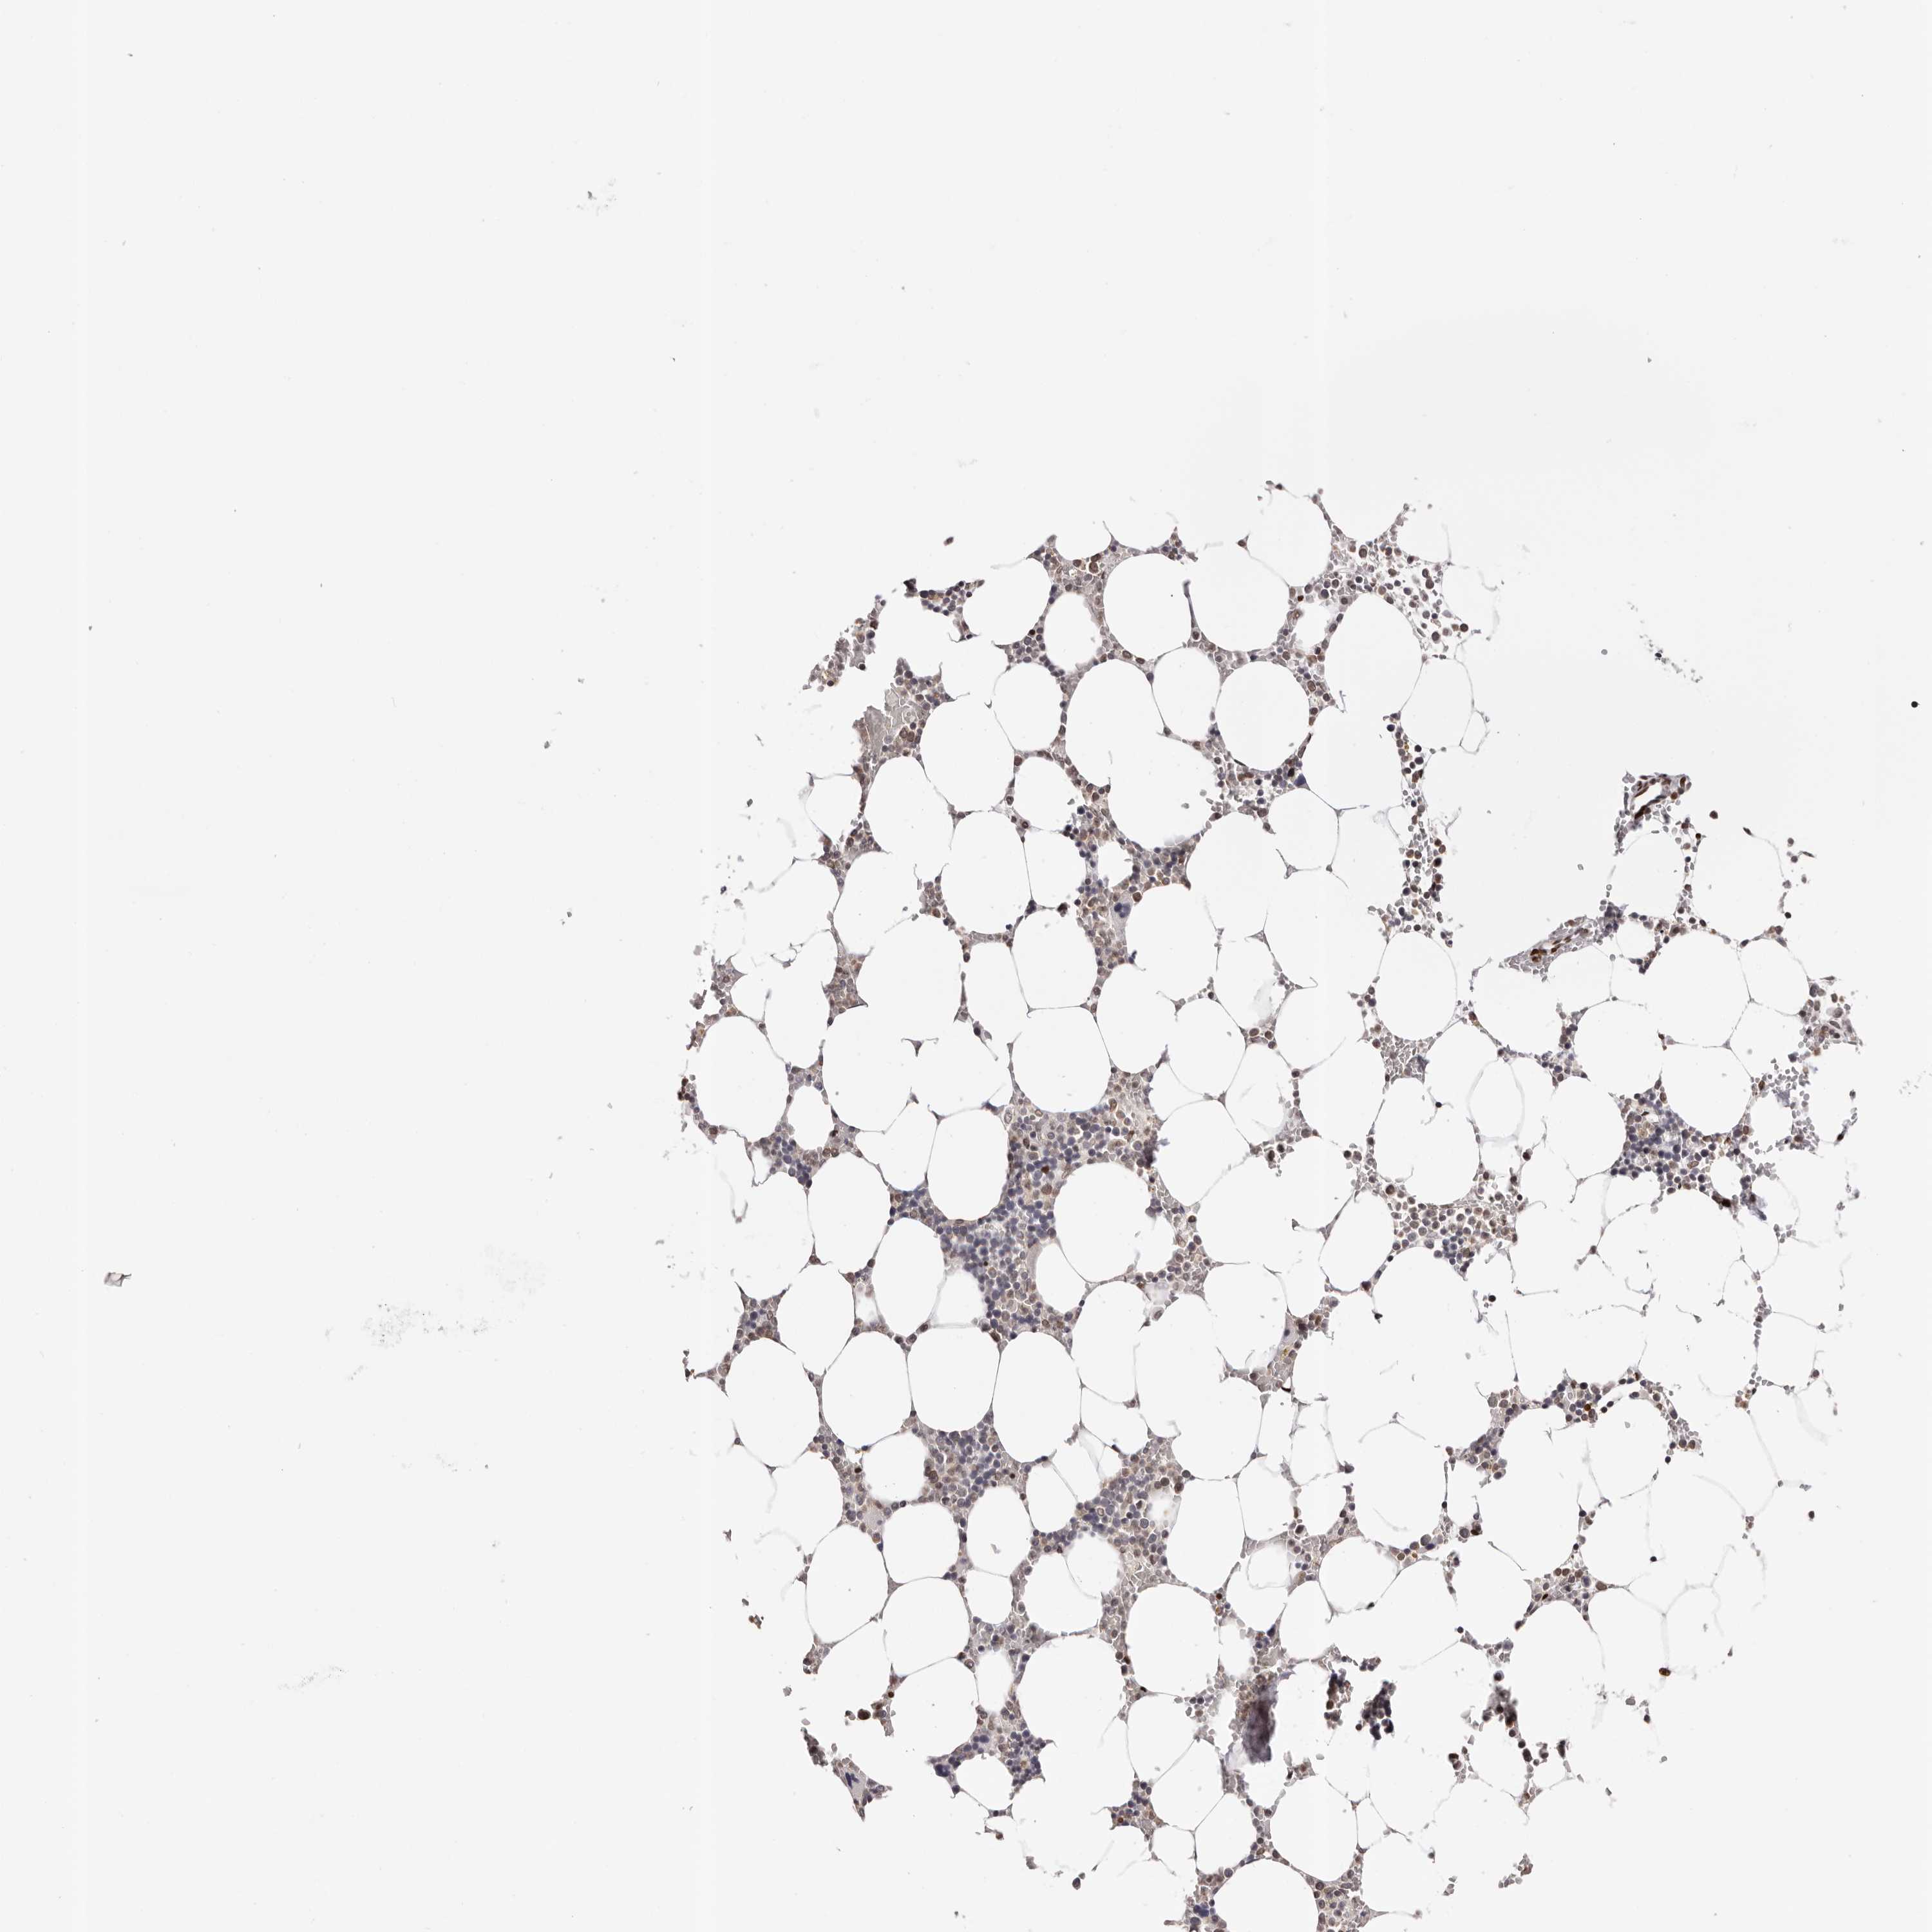

BONE MARROW - HPA RNA-seqi

The RNA-seq details section shows detailed information about the individual samples used for the transcript profiling and results of the RNA-seq analysis.

Information about each individual sample is listed below, including gender, age, a tissue section image and estimated fractions of cell types. nTPM (normalized transcripts per million) values give a quantification of the gene abundance which is comparable between different genes and samples.

Average nTPMi

Max subtype nTPM is the value for the subtype with the largest average nTPM across the subtype samples.

45.0

Female, age N/A

Bone marrow sample 97

nTPM: 53.8

Cell types%

Myelopoietic cells:

50

Erythropoietic cells:

30

Lymphocytes:

10

Monocytes:

5

Blastic cells:

Male, age 68

Bone marrow sample 98

nTPM: 58.5

Female, age 8

Bone marrow sample 99

nTPM: 25.1

Male, age 64

Bone marrow sample 100

nTPM: 42.8